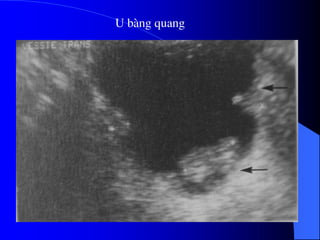

- Siãu ám

Khoï cháøn âoaïn u bãø tháûn, niãûu quaín nãúu

khäng coï æï næåïc âaìi bãø tháûn niãûu quaín.

U baìng quang trãn siãu ám tháúy hçnh tàng

ám trong baìng quang coï næåïc tiãøu räùng ám.

Siãu ám coï thãø tháúy mæïc âäü xám láún thaình

baìng quang vaì ngoaìi thaình baìng quang.